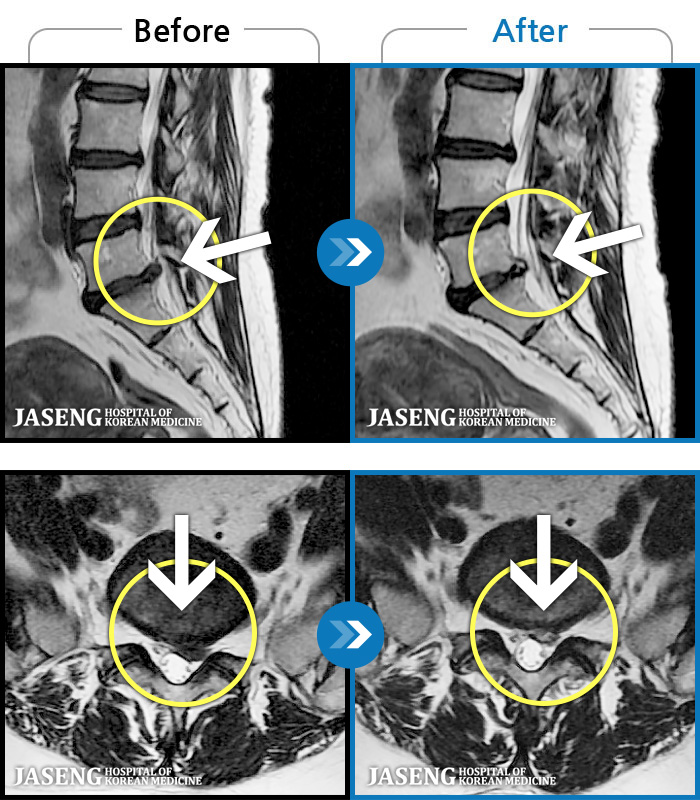

MRI ġ

1,299 MRI ũ ʸ Ȯϼ.